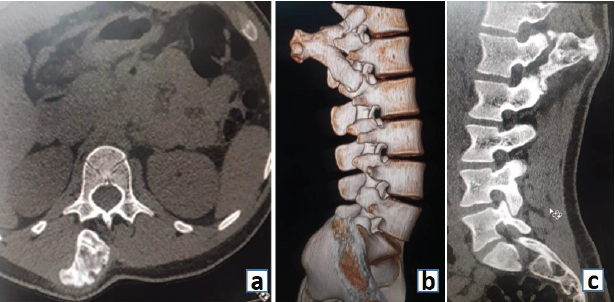

Neurological examination was normal. Computed tomography (CT) scan showed a pedunculated bony outgrowth arising from the right pedicle of L1 vertebral body projecting postero-superiorly, with a fracture at the base (Fig. 2a, b and c). MRI done also showed similar findings and an overlying cartilaginous cap of 2.3 mm thickness. The bony central spinal canal dimensions were normal with no evidence of primary canal stenosis (Fig. 3a and b). Under general anesthesia, an excision biopsy of the tumor mass was done through a posterior approach. Histopathological examination of the specimen as showed in Fig. 4. Postoperatively, the patient was symptomatically better, and on subsequent follow-ups did not show any recurrence or pain.

Figure 2: (a, b and c) Computed tomography scan images as described.